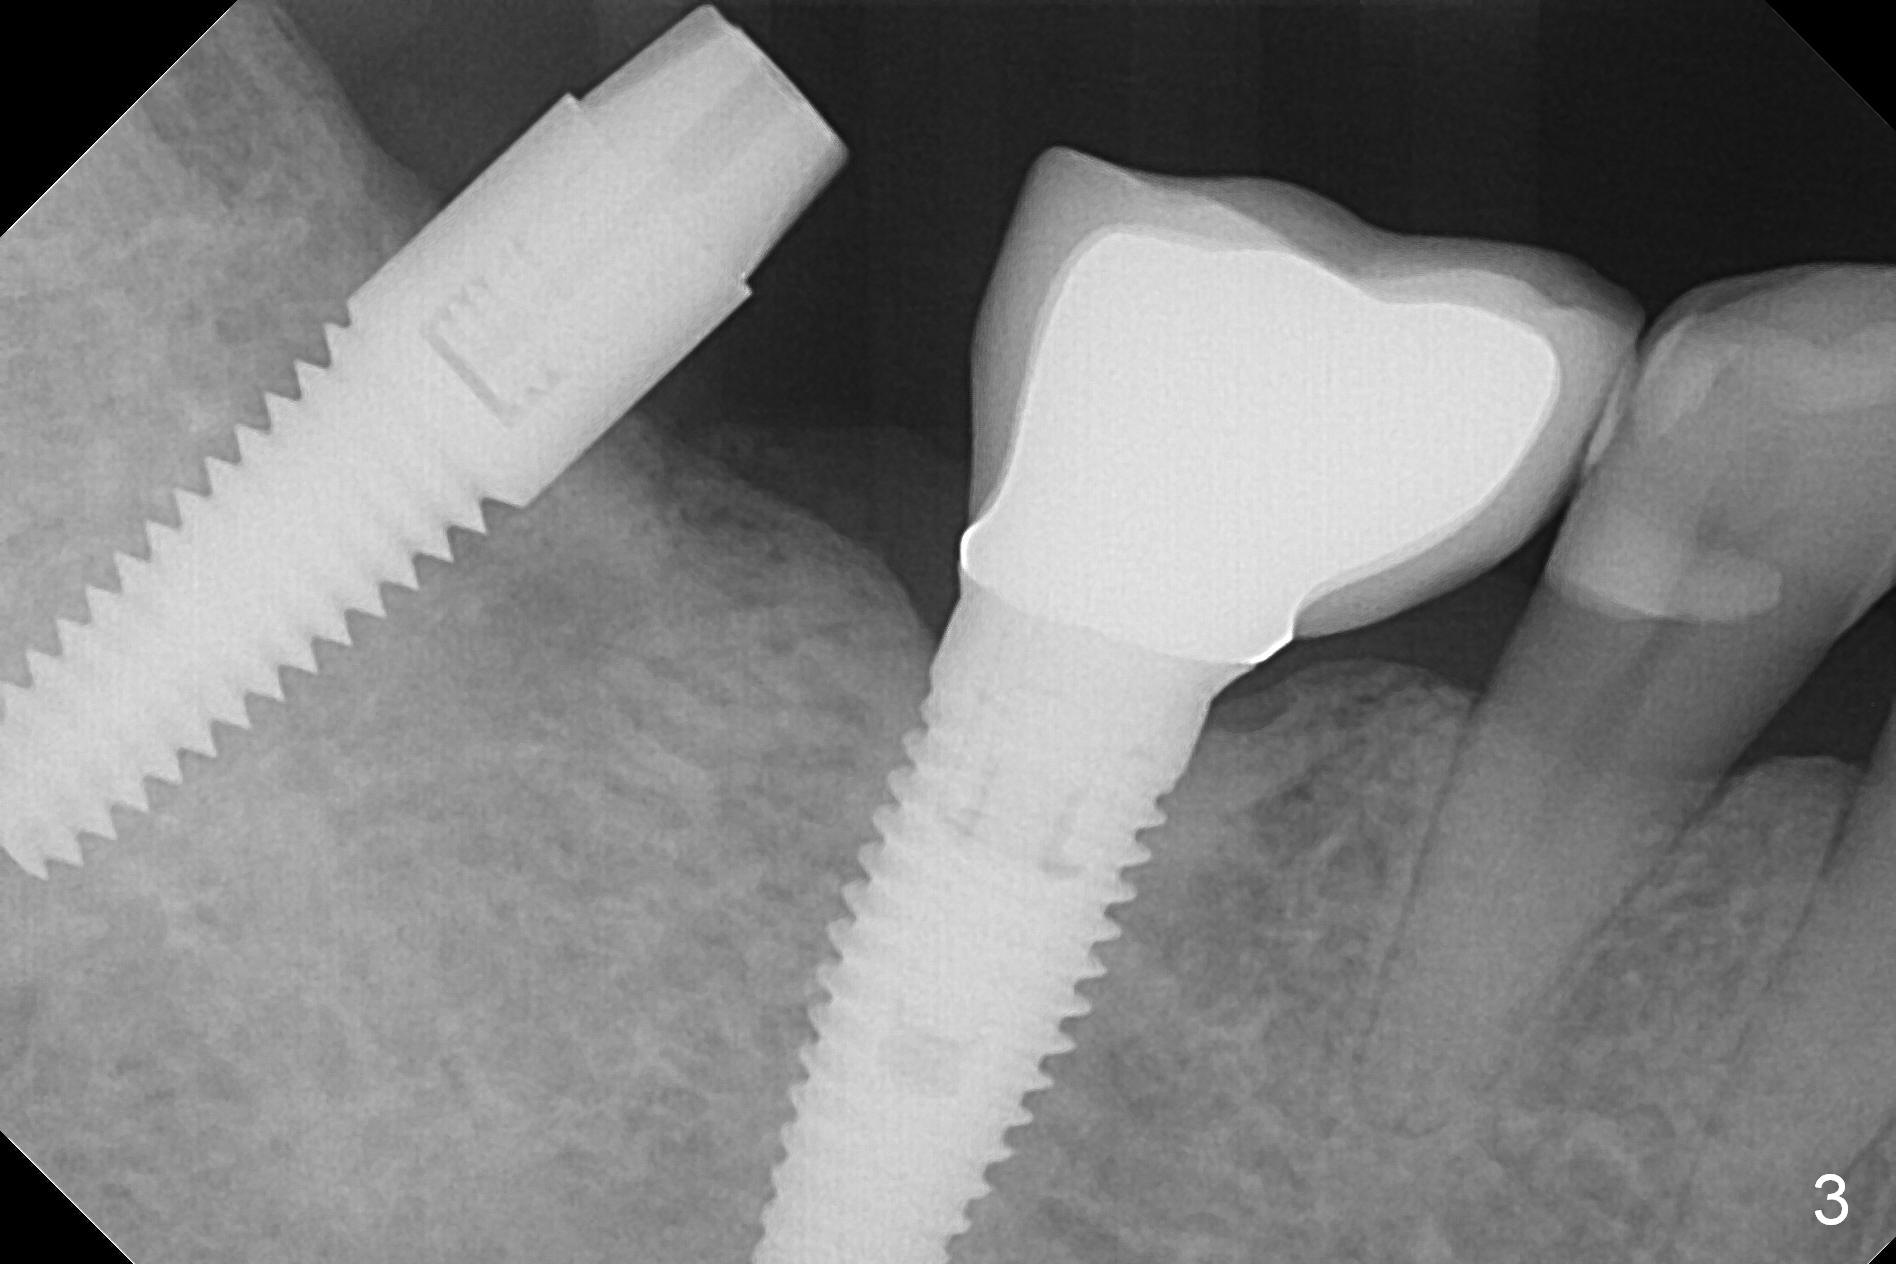

Initial osteotomy at the site of #31 using 2 mm pilot drill for 11 mm appears to be distal by 2-3 mm (Fig.1, Fig.10 A (circle, occlusal view of the edentulous and dentate (#29 and 30) areas)). Lindamann bur is used to move the osteotomy (Fig.8 white rectangle, Fig.10 B). It seems that the osteotomy returns distal as the osteotomy increases (Fig.2 (5x17 mm tap), Fig.8 arrow, Fig.10 C (green circle)). It appears to be late to change; a 5x17 mm tissue-level implant is placed with > 60 Ncm (Fig.3-5). The buccal and lingual rough surface of the implant (Fig.5 *) is covered by autogenous bone/Osteogen and Collagen Dressing (Fig.6 *). After suturing (Fig.7), periodontal dressing is applied around the abutment (Fig.5 A (4.5x3 mm)).

To change osteotomy trajectory and position correctly, it should be overcorrected (Fig.9 white rectangle with *, Fig.10 D).

The patient will return for provisional >`1 month postop with chief complaint "the implant is too high". The 2nd and 3rd options are to place healing screw and healing abutment.